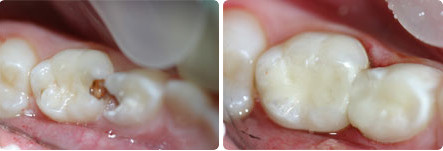

Пульпит молочных зубов: фото до и после